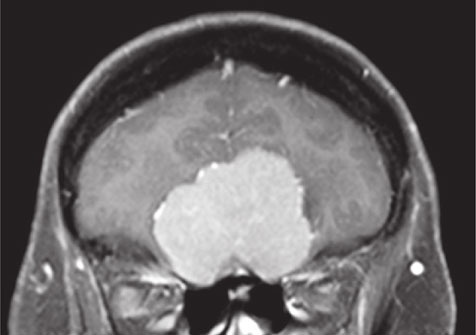

И это на самом деле так. Все повреждения передней части черепа могут нарушить их функционирование. На рисунке 36 можно видеть, как большая менингиома, доброкачественная опухоль, растущая из ткани, окружающей мозг, захватывает его именно в том месте, где обонятельные нервы проникают в череп. Естественно, что аносмия является обычным симптомом при заболеваниях подобного рода.

Иллюстрация к книге — Почему девочки не хуже мальчиков разбираются в математике [i_035.jpg]

Рис. 36. Большая светло-серая масса, расположенная над носовыми полостями, это менингиома; в результате ее разрастания нарушается функционирование обонятельных нервов в том месте, где они проникают в череп